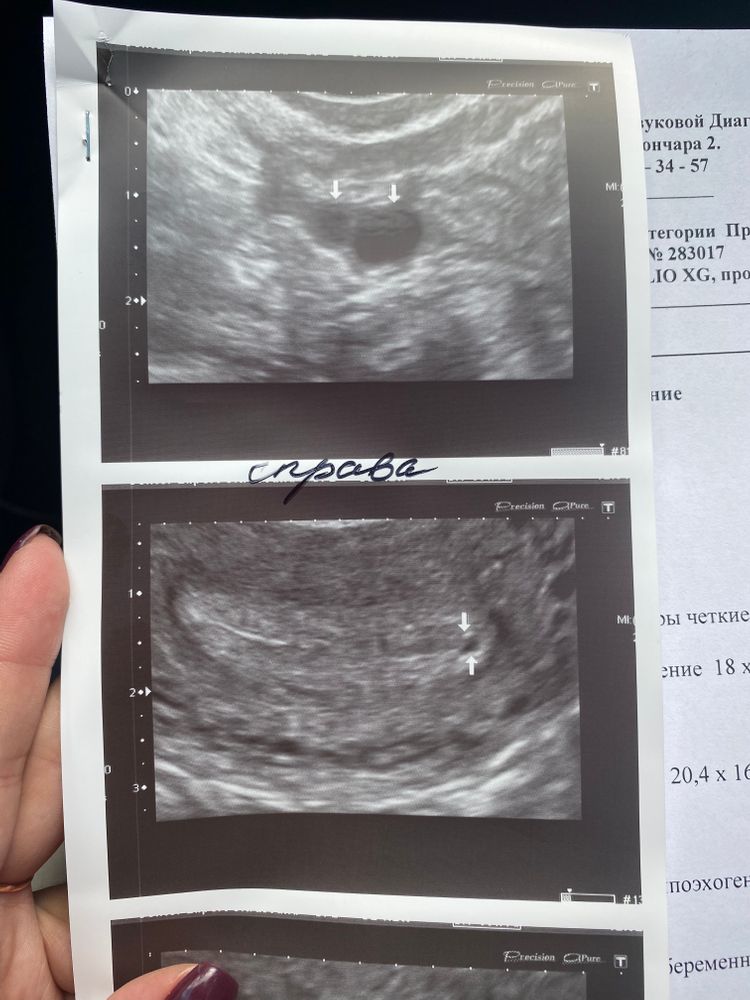

Девочки , сегодня сходила на узи по месячным срок 5.2 недели не нашли плодное яйцо , только какая-то точечка , но узист сказал , что нельзя утверждать , что это оно😩 до сих пор идут коричневые выделения, сказали прийти на узи через неделю . Боюсь внематочной. У кого так же не находили плодное яйцо , а потом нашли ?

Марина, узист сегодня сказала , что для акушерского такого срока плодное яйцо должно быть🥺

да 17го предположительно, но не уверенна , потому что последнее время отпустила ситуацию с планированием и не отслеживала овуляцию